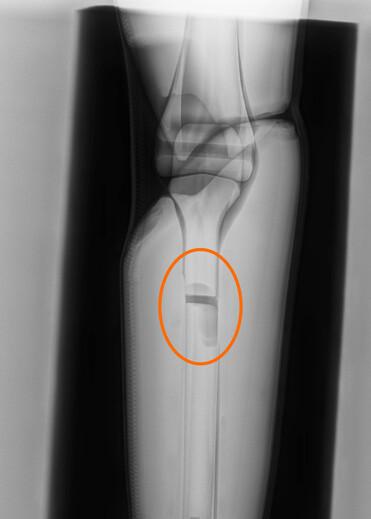

Direkt nach einem Crashtest können durch medizinisches Röntgen Beschädigungen an Knochen- und Gewebeteilen des PRIMUS-Dummys sichtbar gemacht werden. Durch diese direkten Einblicke können so Rückschlüsse auf reale Verletzungen gezogen werden und ermöglichen darüber hinaus eine Einstufung in die vereinfachte Verletzungsskala (Abbreviated Injury Scale (AIS)).

Auswertung der Röntgenbilder, PRIMUS breakable

Beispiel der technische Auswertung anhand des PRIMUS breakable